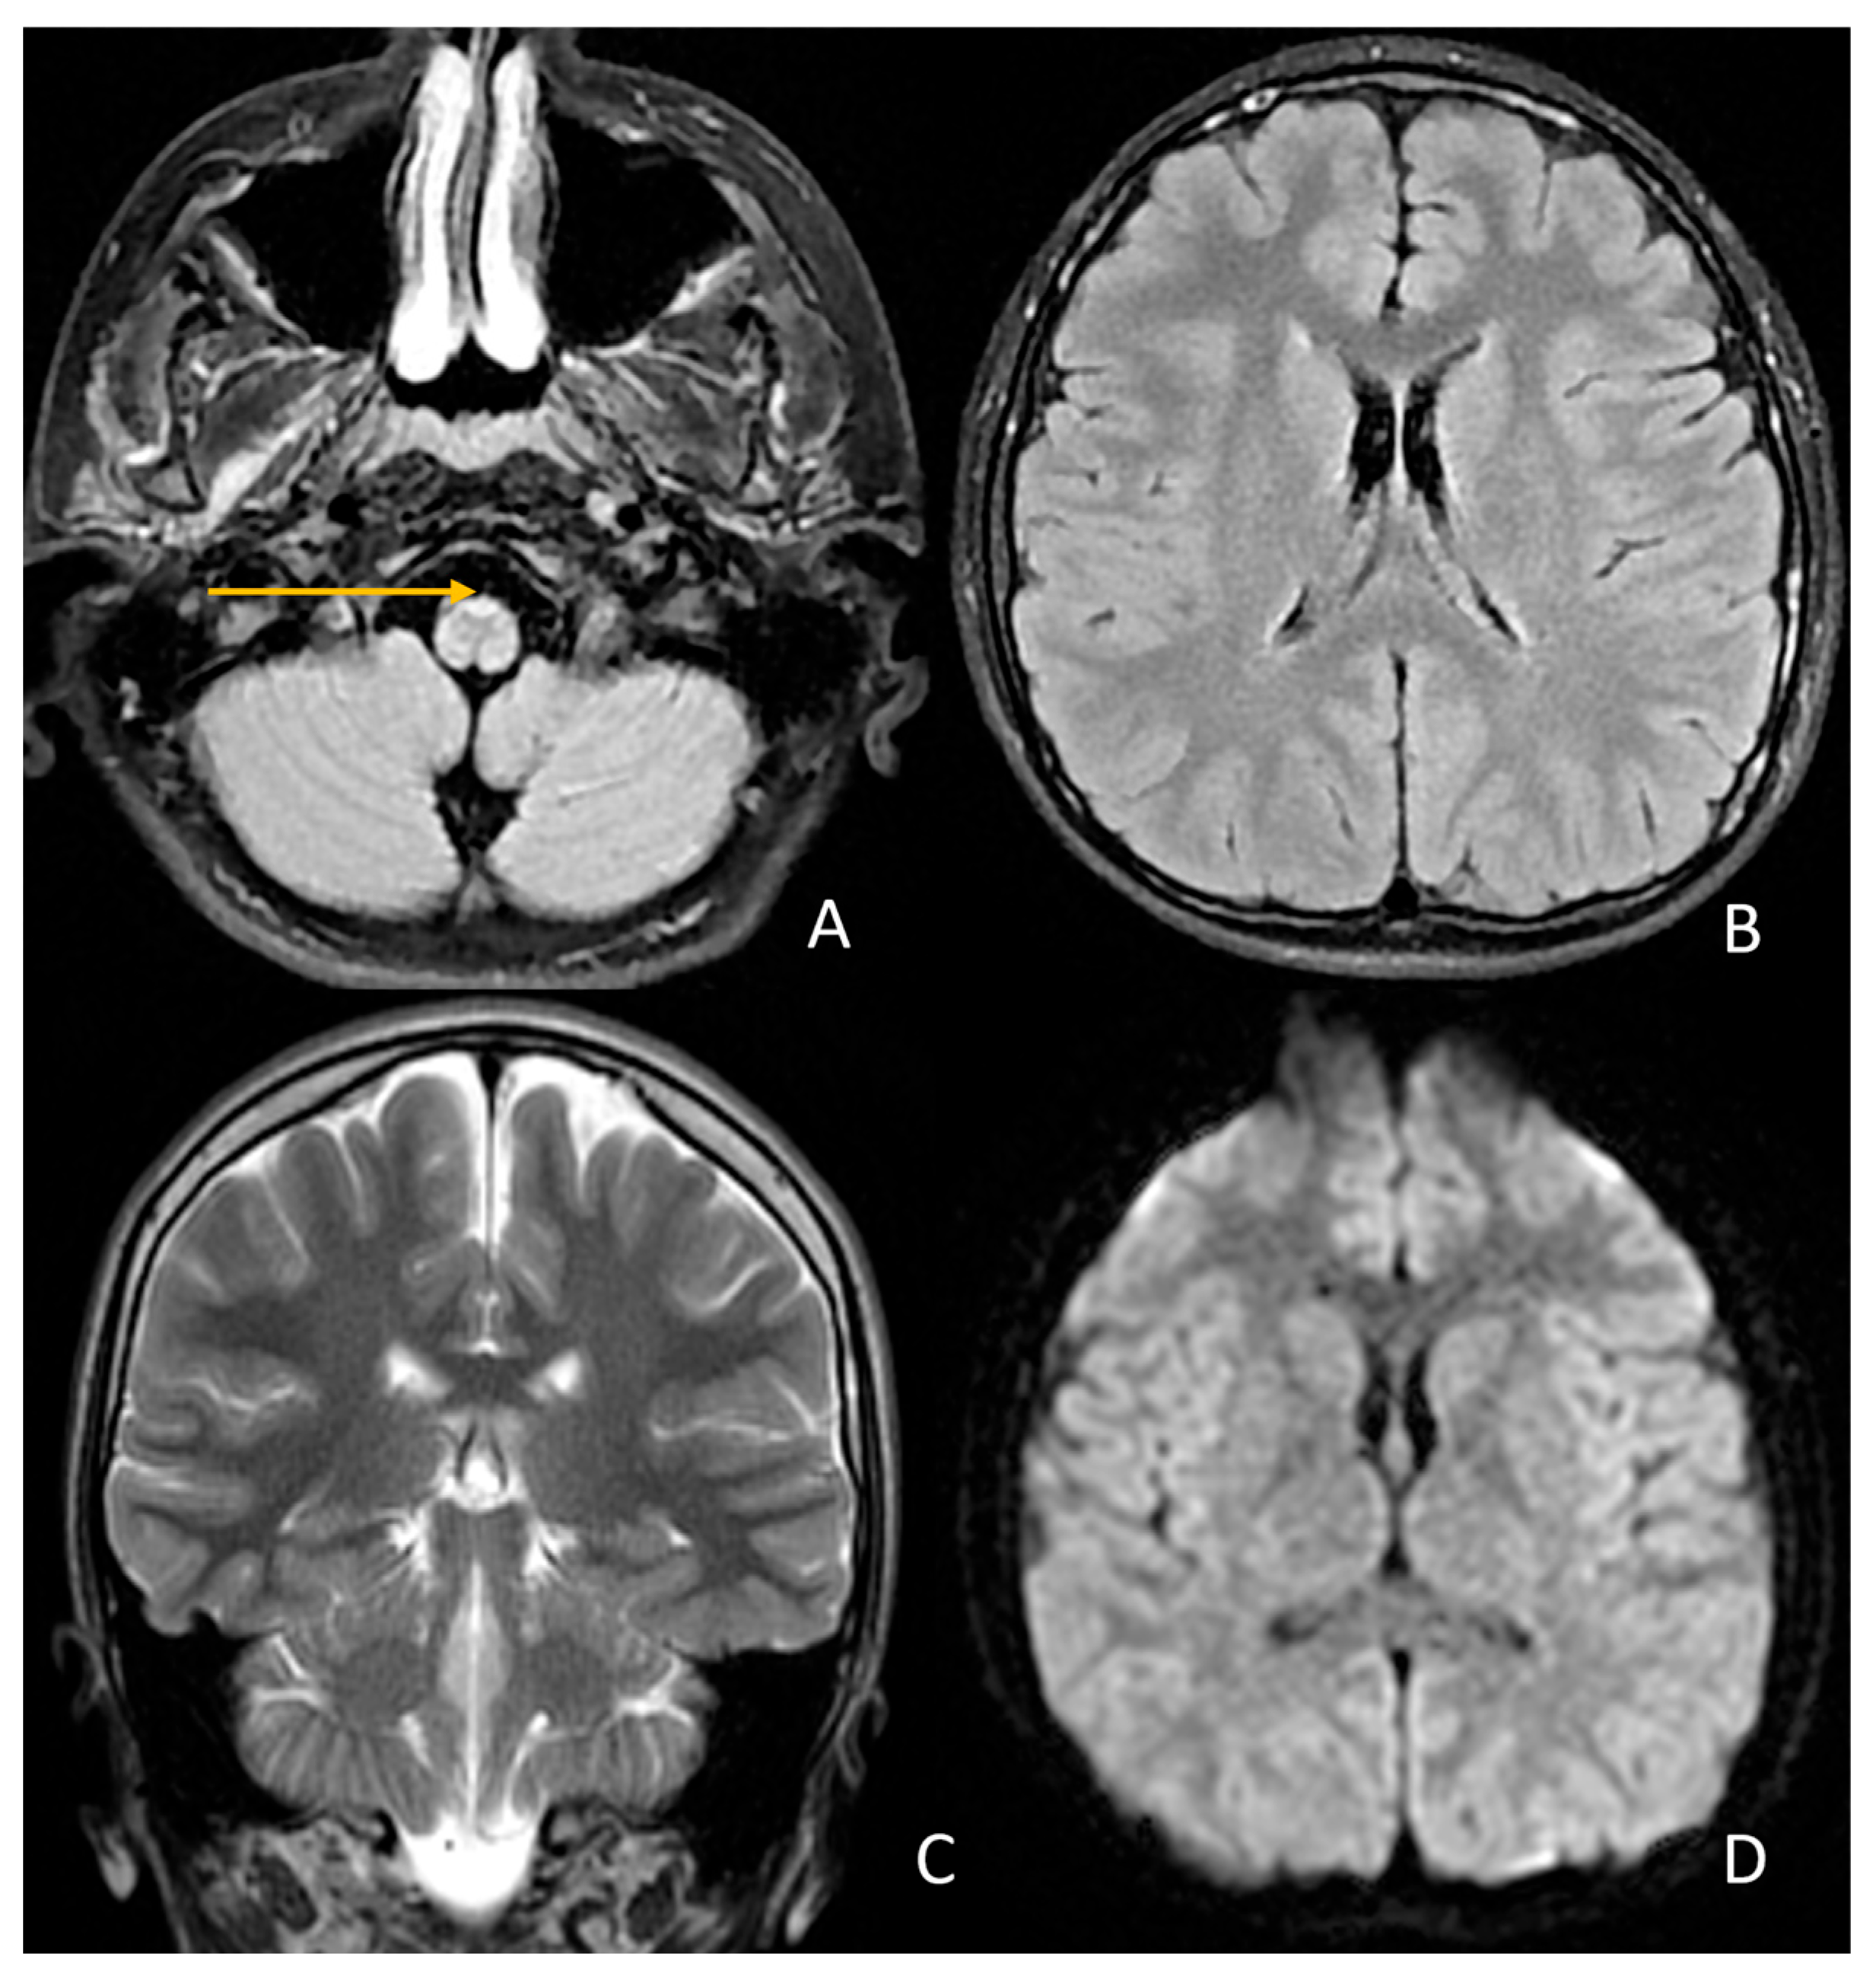

| Abnormal signal intensity of the anterior portion of the medulla oblongata | Yes | NA | Yes | Yes | Yes | Yes | Yes |

| Atrophy of the medulla | No | NA | No | Yes | Yes | Yes | Yes |

| Atrophy of the cervical spinal cord | Yes | NA | No | Yes | Yes | Yes | Yes |

| Signal abnormalities in the cerebellar white matter or hilus of the dentate nucleus | No | NA | No | No | No | No | No |

| Cyst formation in white matter around the anterior horn of the lateral ventricles | No | NA | No | No | No | No | No |

| Ventricular garlands | No | NA | NA | NA | NA | NA | NA |